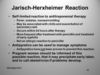

Vancomycin (Inhibits cell wall peptidoglycan formation by binding D-ala D-ala portion of cell wall precursors. Bactericidal. Not susceptible to β-lactamases)

VRE: vancomycin resistant enterococcus (D-ala D-lac) –> alters the cell wall peptidoglycan

Can use Linezolid or tigecycline to tx enterococcus

If no resistance, Ampicillin is first line treatment. Gentamycin may be added in cases of endocarditis